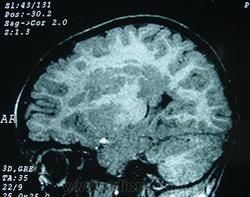

Гетеротопии. Перивентрикулярная гетеротопия. Субэпендимальная нодулярная (узелковая) гетеротопия.

Наиболее частым вариантом миграционных нарушений является гетеротопия - скопление нейронов, остановившихся в различных аномальных местах на пути следования к коре головного мозга. Такая остановка происходит не позже 5-го месяца внутриутробного развития. Изолированный участок узловатой массы называется «гетеротопион». В настоящее время описаны следующие варианты гетеротопии:

Перивентрикулярная субэпендимальная гетеротопия